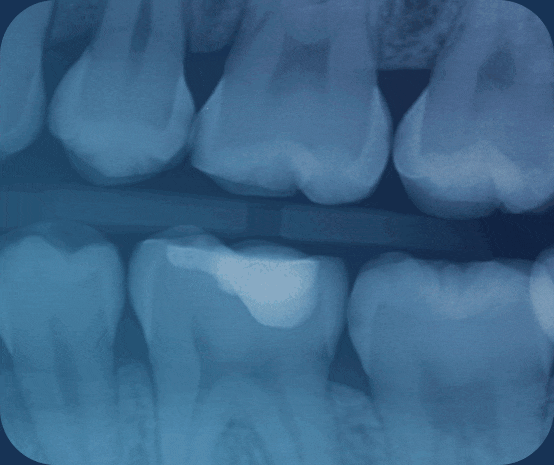

For complex cases, CBCT technology provides unparalleled 3D imaging, solving visibility issues in endodontics, impacted teeth, and oral pathology that 2D X-rays can’t match. In my office, I use CBCT for planning root canals, extracting impacted wisdom teeth or canines, and detecting pathologies like cysts.

In endodontics, CBCT reveals hidden canals, reducing failure rates. For an impacted canine, it guided minimally invasive surgery, minimizing trauma. This precision addresses risks in blind procedures, enhancing safety.